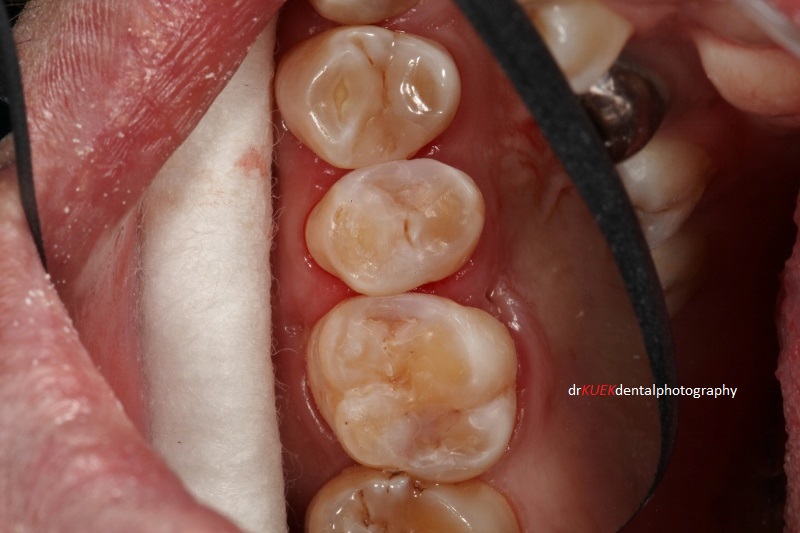

Today I am sharing a case on composite resin fillings to show the importance of radiographs in a thorough dental checkup to detect hidden decayed cavities.

Mr Smith had some decay / cavities in his teeth. Although they were not obvious with a visual examination, they could be detected on the radiograph taken during his dental checkup.

Shades of composite resin materials were chosen and tints were used to create the fillings, aimed to blend the fillings with the natural teeth.

Shades of composite resin materials were chosen and tints used to create the fillings, aiming to blend the fillings with the natural teeth.